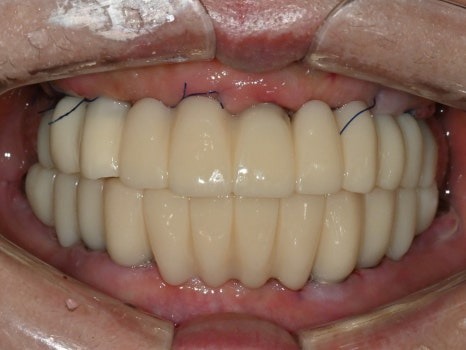

수술 당일

수술 2일 후

직장에서 시간을 내기가 어려우신 상황이라

토요일 오전,

수면마취로 17개의 임플란트를 식립하였고,

월요일에 임플란트 즉시 기능 치아(임시치아)를 끼워드렸습니다.

치료 전

수술 2일후

몇 개월이고 기약 없이 임시 틀니를 써야한다는 걱정에

치료를 시작하지 못하셨던 환자분은

수술 2일 만에 고정된 치아가 완성되자

놀라워하시면서 식사가 가능하게 된 걸

너무 좋아하셨습니다.